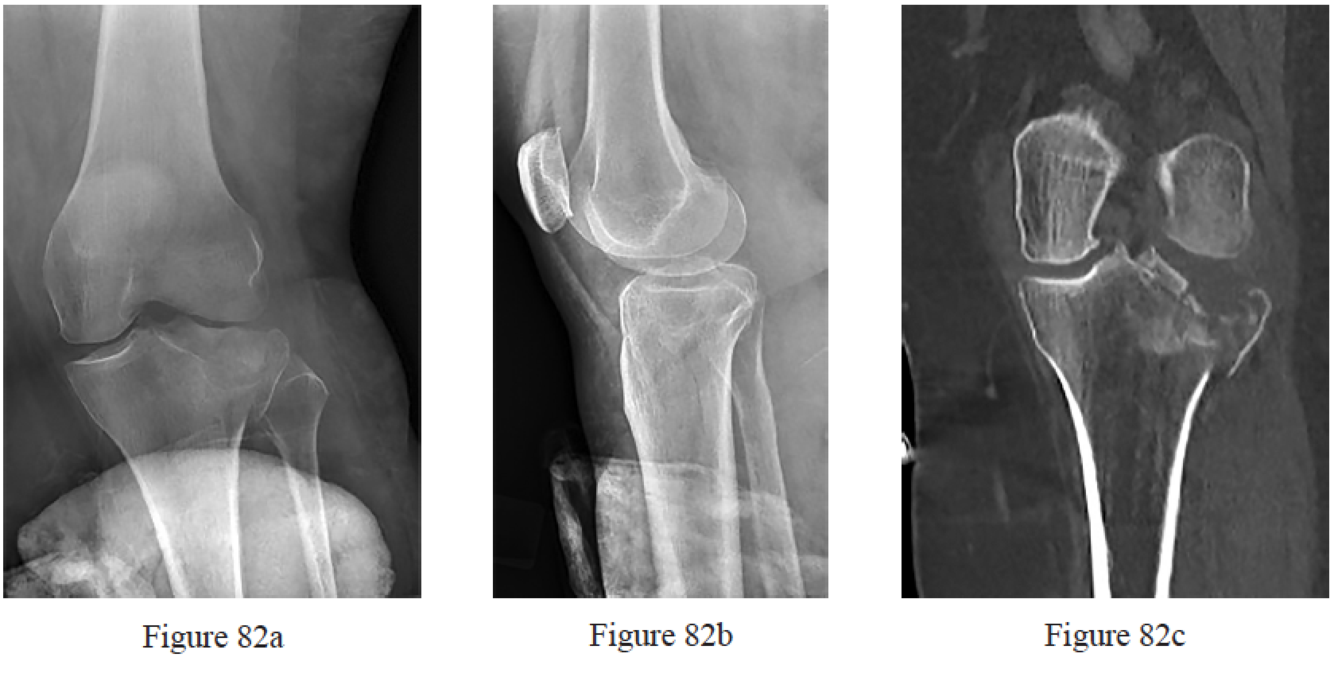

commonly injured?

Gardner MJ, Yacoubian S, Geller D, Pode M, Mintz D, Helfet DL, Lorich DG. Prediction of soft-tissue injuries in Schatzker II tibial plateau fractures based on measurements of plain radiographs. J Trauma. 2006 Feb;60(2):319-23; discussion 324. PubMed PMID: 16508489.

Gardner MJ, Yacoubian S, Geller D, Suk M, Mintz D, Potter H, Helfet DL, Lorich DG. The incidence of soft tissue injury in operative tibial plateau fractures: a magnetic resonance imaging analysis of 103 patients. J Orthop Trauma. 2005 Feb;19(2):79-84. PubMed PMID: 15677922.